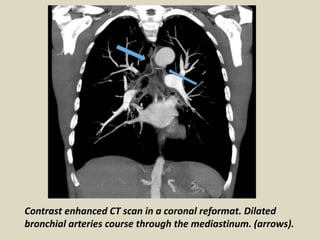

Vascular abnormalities.

Dilated bronchial arteries. These are best

demonstrated post administration of intravenous

contrast. These tortuous vessels extend along the

central airways toward the hila. It is these vessels that

are often responsible for hemoptysis, a symptom

these patients may describe.

Contrast enhanced CT scan in a coronal reformat. Dilated

bronchial arteries course through the mediastinum. (arrows).